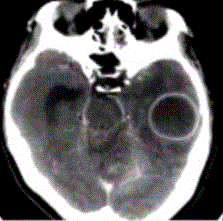

问题 患者女,26岁,头痛、低热10d余,既往有左侧慢性中耳炎病史。CT表现如下图。 有关脑脓肿的DWI表现,正确的是

选项 A.DWI上脓肿腔均呈高信号,ADC呈低信号 B.经过治疗的脓肿腔DWI也可呈等信号或低信号 C.DWI脓肿周围水肿高信号,ADC高信号 D.DWI上脓肿腔低信号,ADC高信号 E.脓肿壁DWI高信号